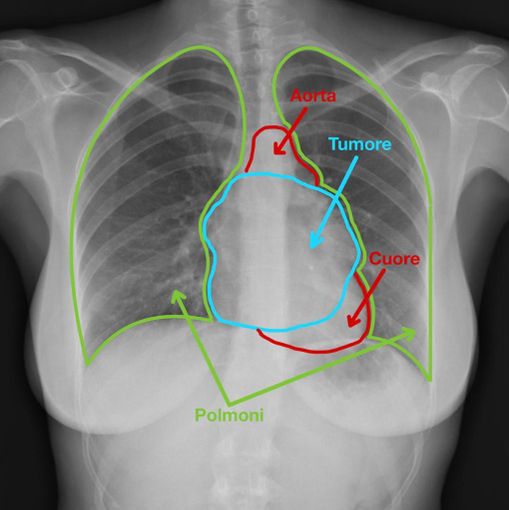

La sfida, in questo caso, era di riuscire ad asportare un tumore di così grandi dimensioni, localizzato sopra il cuore e l’aorta, mediante l’utilizzo del robot, guidato dal chirurgo toracico. I dottori Paraskevas Lyberis e Francesco Guerrera, della Chirurgia Toracica universitaria (diretta dal professor Enrico Ruffini), hanno utilizzato una tecnica chirurgica modificata, avvalendosi del robot, mediante l’utilizzo di nuovi traccianti fluorescenti che hanno consentito di asportare la grossa massa toracica senza lasciarne alcun residuo nè danneggiare polmoni e cuore.